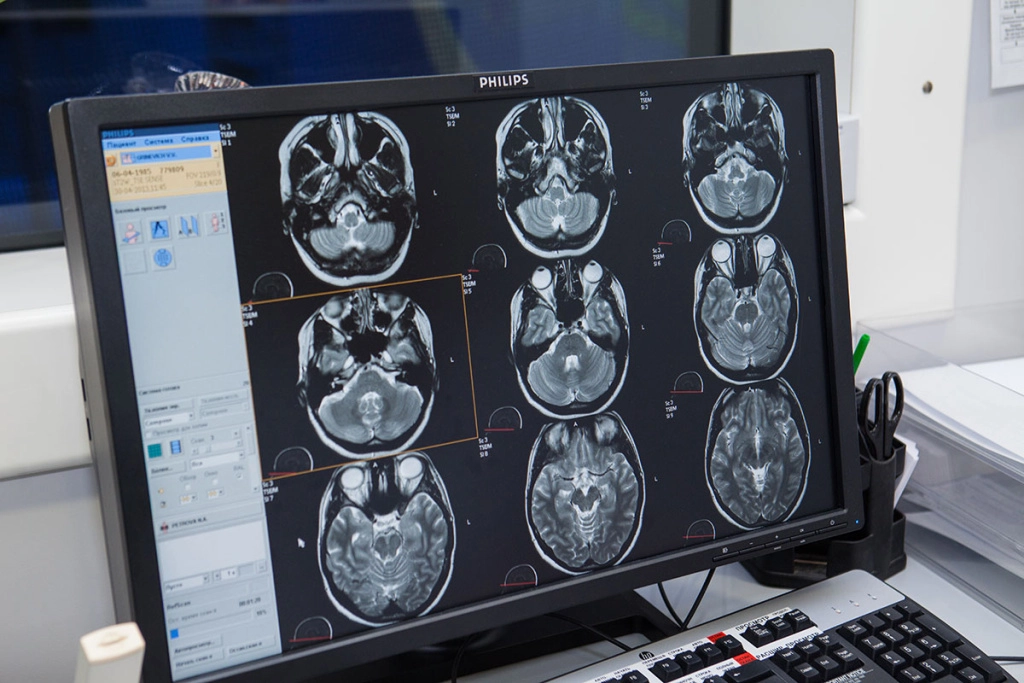

Томография головного мозга – это процедура, которая не занимает слишком много времени. Она направлена на то, чтобы своевременно обнаружить нарушения структуры органа, злокачественные опухоли, метастазы, а также прочие проблемы. Для проведения МРТ используется специализированное оборудование, способное показать максимально точные результаты обследования.

Заключение доктора и расшифровку результатов. Данный процесс может занять всего несколько часов. Но в некоторых ситуациях расшифровка отнимает несколько дней. Все зависит от того, насколько загружен специалист, а также от сложности ситуации со здоровьем пациента. Помните о том, что частные организации работают намного быстрее, чем учреждения государственного типа. В современных центрах и клиниках на практике применяется оборудование, которое обладает наивысшим уровнем качества и показывает максимально точные результаты. Всего за 45 минут можно получить изображения, которые демонстрируют головной мозг со всех сторон. После этого специалист расшифрует все результаты, подробно объяснит их вам, назначит оптимальную схему терапии.

Контраст дает возможность получить четкие и детальные снимки. Данный вариант оптимален в том случае, если речь идет о патологиях сосудов, наличии злокачественных опухолей, распространении метастазов и так далее. Длительность томографии, которая проводится с применением контрастного вещества, более значимая. Зависит это от того, насколько хорошо человек переносит компонент, а также от размеров той области мозга, которая подлежит обследованию. Контраст способствует тому, что длительность процедуры увеличивается минимум на полчаса. В некоторых ситуациях необходим специальный тест, проверяющий чувствительность человека к веществу.

Это дополнительные временные затраты. Если говорить о среднем времени, то МРТ с контрастом длится не менее часа. Специалисту может понадобиться до 90 минут, если он будет заниматься комплексной диагностикой организма. На сегодняшний день МРТ – это инновационный метод обследования, который даст возможность изучить состояние головного мозга во всех подробностях. Благодаря такой процедуре можно точно обнаружить те патологии, которые являются скрытыми или же выраженными. Специалист поставит точный диагноз в индивидуальном порядке для каждого пациента, а также составит схему терапии, которая даст возможность избавиться от существующих проблем со здоровьем. Главное, чтобы вы нашли хорошую клинику. Внимательно читайте отзывы о ней, чтобы диагностикой головного мозга и его лечением занимались квалифицированные профессионалы.